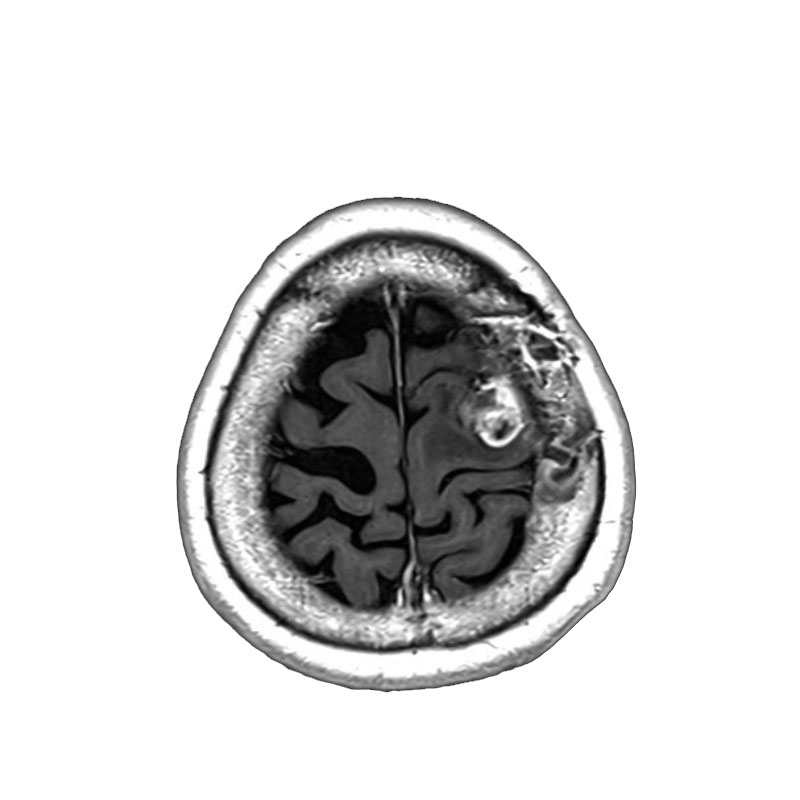

右小脳腫瘍

摘出術

北野